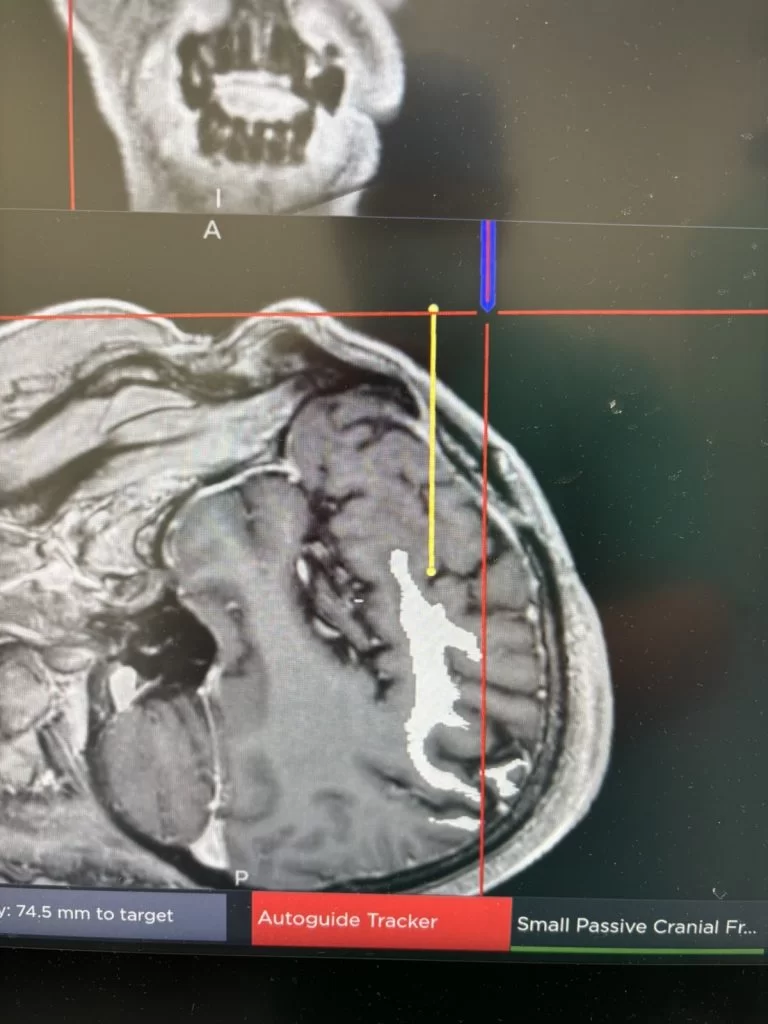

Η εξάχνωση με λέιζερ αποτελεί μια ελάχιστα επεμβατική τεχνική, κατά την οποία τοποθετείται ένας λεπτός καθετήρας εντός του όγκου και, με τη βοήθεια ελεγχόμενης θερμότητας, ο όγκος καταστρέφεται. Σε σύγκριση με την ανοιχτή χειρουργική επέμβαση, πρόκειται για μια σαφώς πιο ασφαλή μέθοδο, με σημαντικά ταχύτερη ανάρρωση για τον ασθενή. Επιπλέον, η τεχνική αυτή επιτρέπει τη λήψη ιστού για βιοψία πριν από την καταστροφή του όγκου, γεγονός ιδιαίτερα σημαντικό για τη σωστή διάγνωση και περαιτέρω αντιμετώπιση.

Το πλεονέκτημα του λέιζερ, πέραν του ότι είναι πολύ λιγότερο επιβαρυντικό για τον ασθενή, είναι ότι η επέμβαση ουσιαστικά πραγματοποιείται στον μαγνητικό τομογράφο και έχουμε τη δυνατότητα να παρακολουθούμε το αποτέλεσμα σε πραγματικό χρόνο (real time).

Στην προκειμένη περίπτωση η βλάβη καταστράφηκε πλήρως.